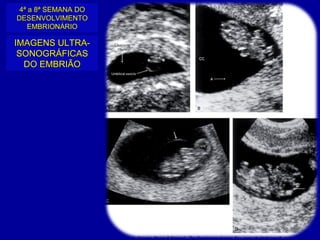

4ª a 8ª SEMANA DO

DESENVOLVIMENTO

EMBRIONÁRIO

IMAGENS ULTRA-

SONOGRÁFICAS

DO EMBRIÃO